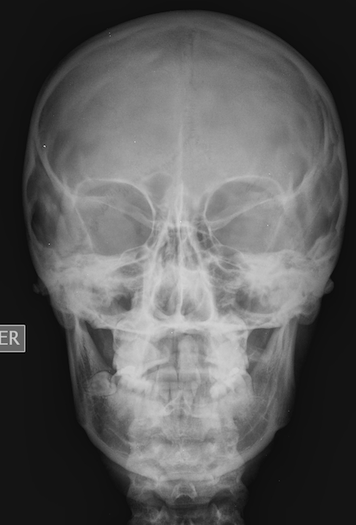

En el siguiente ejemplo, la probabilidad pretest de tener un cáncer de pulmón en pacientes hombres mayores de 65 años, fumadores con consumo acumulado de 60 paquetes/año, con síndrome consuntivo, hemoptisis y tos irritativa de más de tres meses, sabemos que es del 90 %, la RV positiva de 94 y la RV negativa 0.006. Aplicando la línea en el nomograma de Fagan, se obtiene una probabilidad positiva postest de > 99 %, y una negativa postest del 3 %. Esto significa que, en nuestro grupo de pacientes referidos, más del 99 % de los pacientes con radiografía de tórax patológica tendrá un cáncer de pulmón y que, si la radiografía de tórax es normal, sólo lo tendrán un 3 %, tal como se observa en el siguiente nomograma.